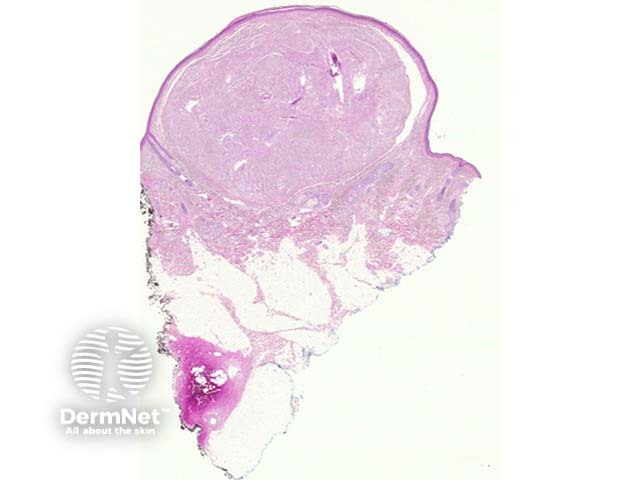

Palisaded and encapsulated neuroma is a circumscribed dermal tumour underlying an uninterrupted or attenuated epidermis (figure 1). A split between the tumour and the surrounding dermis is often seen (figures 1, 2).

Figure 1